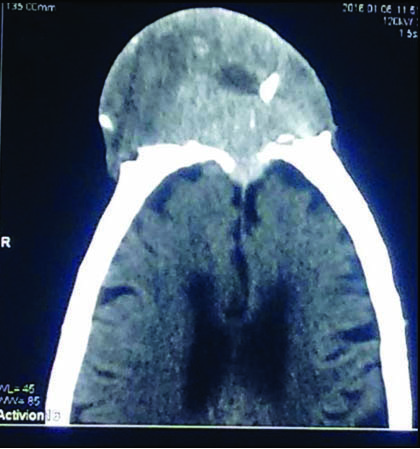

Computed Tomography (CT) of the brain showed a well-defined heterogenous soft tissue density lesion in the midline located mainly in the pre frontal region with internal calcification. The underlying lesion showed erosion and destruction of the bone with intracranial extension. The lesion was limited by the duramater and measured 9x6.5 cm, extending upto the frontal sinus and nasion [Table/Fig-3]. Skin over the lesion appeared stretched.

CT brain without contrast showing well defined heterogenous soft tissue density, with internal calcification, eroding the frontal bone. (left to right)